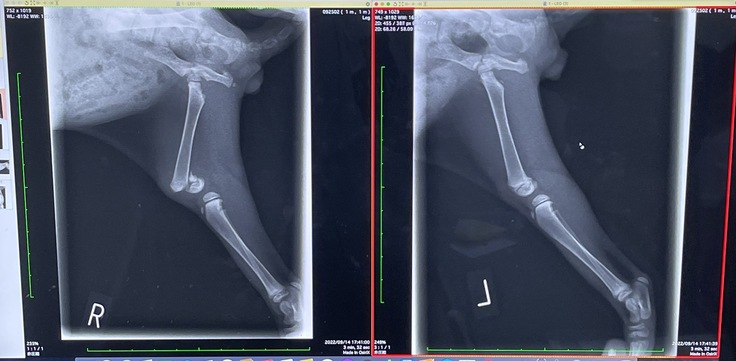

【『右大腿骨骨折』という診断‼】

骨端線(骨の成長点)を損傷しており、関節に近いこともあり、このまま放置すると関節ごと固まって足が使い物にならなくなるかもしれないと説明を受け目の前が真っ白になりました。

(↓左:骨折した右足の骨 右:正常な左足の骨)